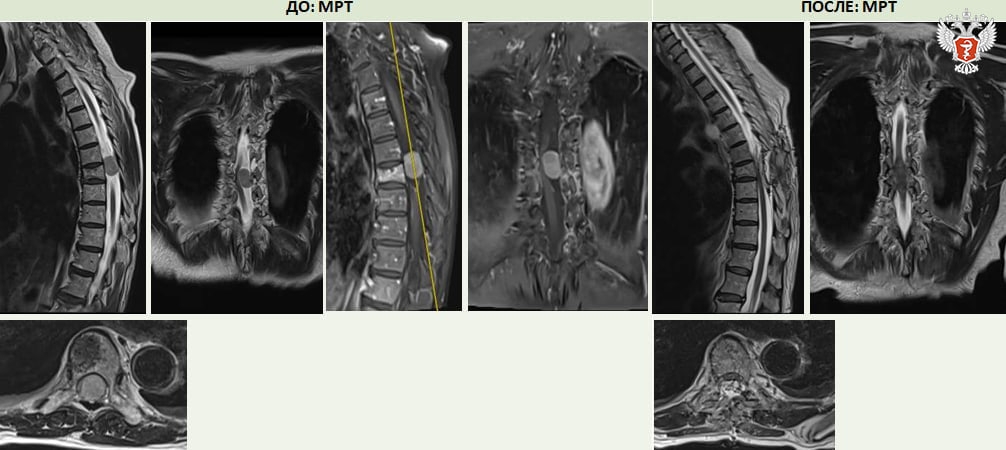

➡ Из-за опухоли в грудном отделе позвоночника у нее полностью пропала чувствительность в левой ноге, возникло нарушение функции тазовых органов, развитие паралича.

— Во благо сработало много факторов: и оперативность помощи, и правильность выбранной тактики лечения, и технические ресурсы нашего центра. Объем опухоли порядка 2-2,5 см, канал был перекрыт полностью, компрессия спинного мозга феноменальная, шанс регресса неврологической симптоматики был минимальный, но дальнейший результат нас просто привел в восторг, такого не ожидалось, — рассказал нейрохирург отделения №15 НМИЦ травматологии и ортопедии им. ак. Г. А. Илизарова Минздрава России Сергей Алексеев.

❤ Сейчас пациентка чувствует себя хорошо: чувствительность в левой ноге полностью восстановлена. После прохождения курса реабилитации она начала передвигаться с использованием средств опоры.